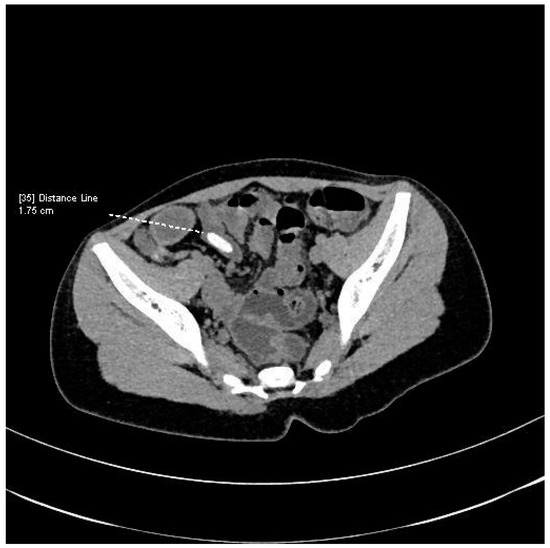

1.1. Case Presentation

1.2. Investigations